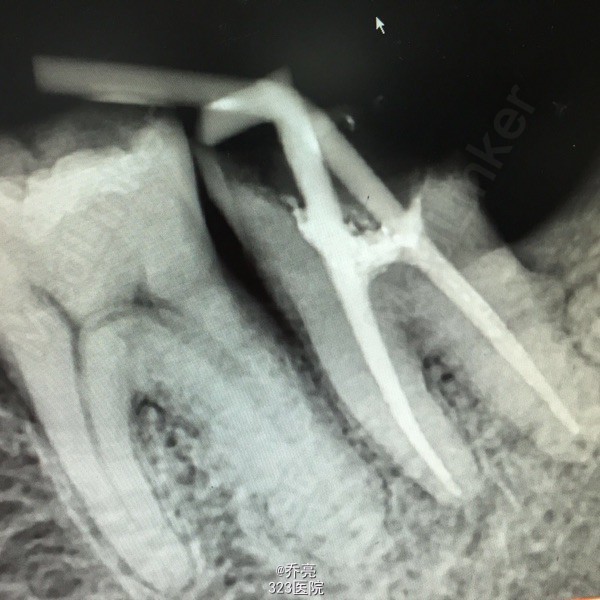

左下7金属牙冠松动,不密合,去除后牙体缺损,面积较大,探(+)冷(+)松动1度,叩(+-) 右上1松动2度 x线示:左下7缺损及髓,根尖无明显异常 右上1根尖阴影

诊断:左下7慢性牙髓炎 右上1牙槽骨吸收 建议:左下7RCT+桩+冠 右上1抜除后修复 处理:左下7清理根管,双氧水冲洗,干燥置木溜油棉,ZOE暂封 右上1局麻下拔除,牙槽窝搔刮,恢复牙槽窝,咬干棉球止血